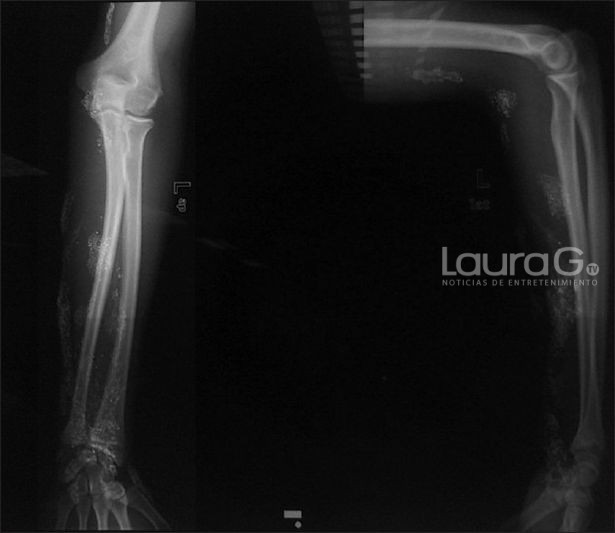

“Informamos del caso de un niño de 15 años que se inspiró en una película y se inyectó deliberadamente mercurio por vía subcutánea en el antebrazo, lo que provocó la formación de una úlcera que no cicatrizó. La histopatología de la biopsia confirma el diagnóstico. Curiosamente, ha tenido múltiples picaduras de araña en el pasado para simular a Spider-Man. Se realizó un procedimiento quirúrgico para tratar la úlcera y reducir los niveles de mercurio en sangre y orina”, se lee en el informe.